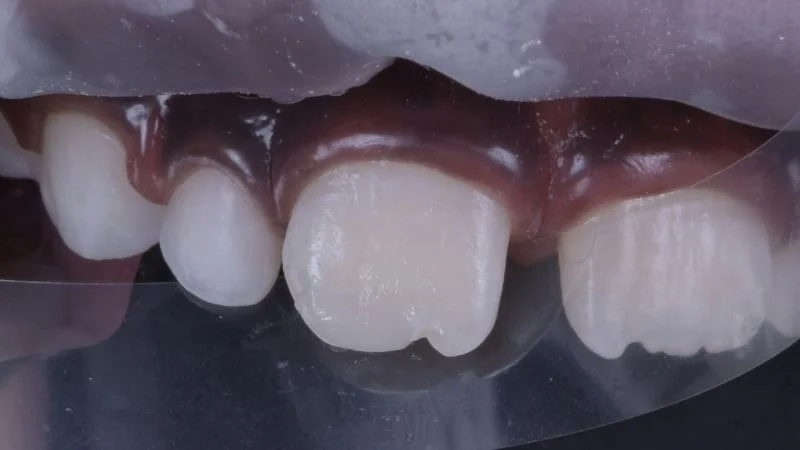

Detailansicht des frakturierten Zahnes.

Ansicht von lateral.